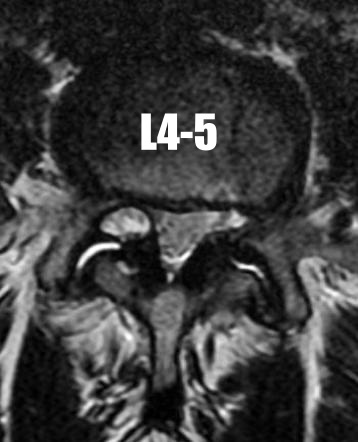

• What is the finding and what condition is this associated with?

• What level is most common?

• symptoms?

• treatment?

Facet Cyst (juxtalumbar facet cyst)

- L4-5 most common level (63%)

- Causes lateral recess stenosis, symptoms to the traversing nerve root.

- Highly associated with degenerative spondylolisthesis (82%).

- Presentation is indistinguishable from that of a herniated disk

- MRI: high signal intensity on T2-weighted image sequencing. It appears to be contiguous with the hypertrophied right facet joint, which appears to also have high signal intensity.

- Is it unstable radiographically? pre-operative flexion-extension films to evaluate for instability to include a potential fusion.

○ Yes:** laminectomy, cyst excision w/ instrumented fusion**

* Presence of instability potentiates recurrence of cyst

* Lower rate of recurrent back pain compared w/ laminectomy alone.